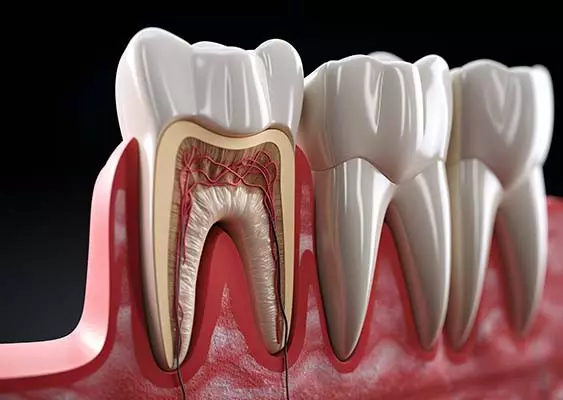

W tym wydaniu m.in: zapalenie przyzębia a ryzyko otępienia, gojenie zmian okołowierzchołkowych, okolica przyszyjkowa jako kompleksowe spojrzenie kliniczne, WawaDent 2024, by-pass złamanego narzędzia.